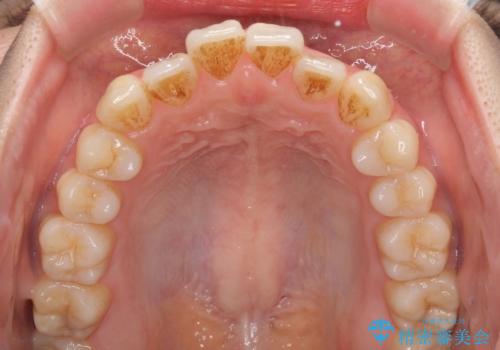

オープンバイトでかみにくい インビザラインによる矯正治療

- 前歯の上下スペースによる食べにくさを気にして来院された患者様です。

インビザラインにより上下の前歯の隙間を閉じていくこととしました。

上下の奥歯を圧下させるようにすることで、前歯を接触させるように計画しました。

上下の隙間に舌が入り込むことがオープンバイトの原因であったため、舌の筋肉のトレーニングも並行して行い、後戻りの抑制を図りました。